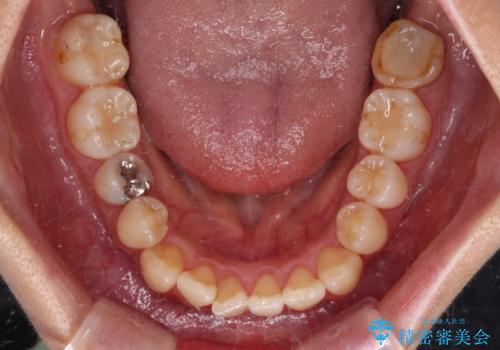

- 前歯のクロスバイトを改善したいとのことで来院された患者様です。

左下の奥歯は根管治療後に放置されていたため、咬み合わせを調整しながら矯正治療を行い、最後にオールセラミッククラウンにて補綴治療を行うこととしました。